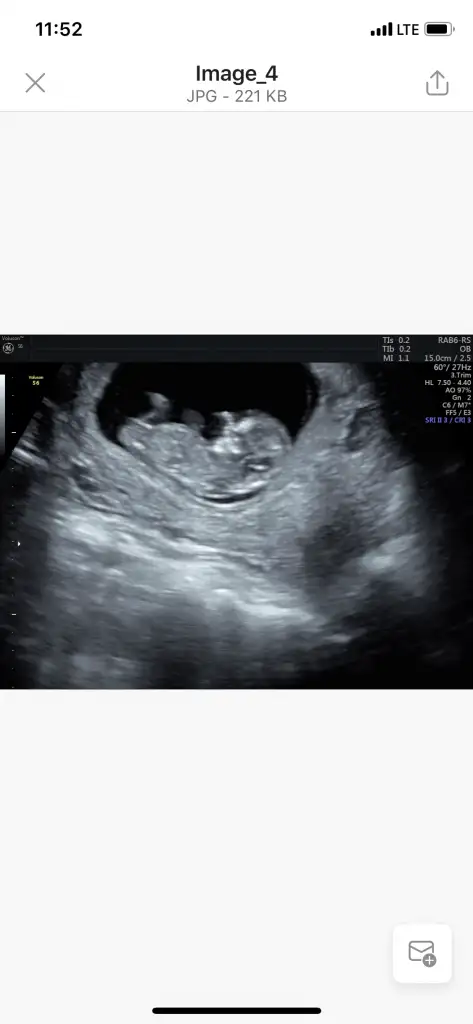

Çok net değil canım bir tahmin edicem olursam kız sankiikra meyra biz tahmin icin haziriz canim minnagim 13+3 doktorumuz kesin olmamakla birlikte bi tahminde bulundu

Çok net değil canım bir tahmin edicem olursam kız sankiemin degilim ama başka usg varmı

Yani hiç net değil usg ama yinede belli olmaz daha erken dr kesin dediği zamanı bekleBaska usg yok canim doktor erkege benziyor gibi dedi kesin bisey demedi,, aslinda bacak arasini gosteren bi ani vardi dr onu yakalayamamis cekerkenkese tahminin tuttu ozaman erkek demistin

Erkek gibi sanki 13 hafta usg de paylaşınMerhaba 11+0 günlük usg yorum yapabilir misiniz

Doktorumuz kıza benzetti bakalım hayırlısı öğrenince pylaşırım☺ Birkaç usg daha var onları da ekliyorumErkek gibi sanki 13 hafta usg de paylaşın

Net değil 12-13 hafta olursa paylaşınDoktorumuz kıza benzetti bakalım hayırlısı öğrenince pylaşırım☺ Birkaç usg daha var onları da ekliyorum

Kız sanki emin olamadım başka usg de paylaşınBanada tahmin yapabilirmisiniz 12 haftalık